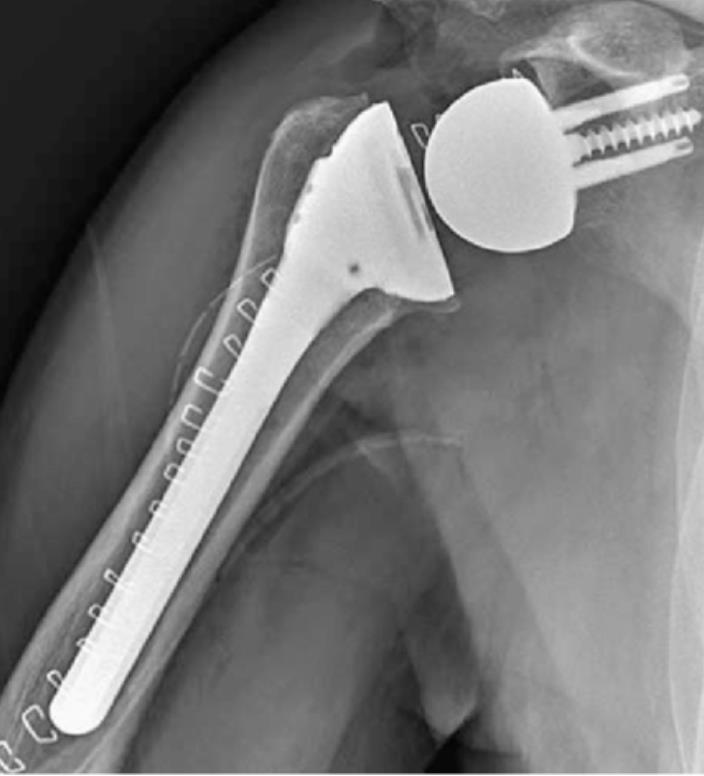

[Blocked from Release] AltiVate Reverse®

• The AltiVate Reverse Shoulder System by Enovis is a reverse shoulder arthroplasty platform designed to restore mobility in patients with rotator cuff deficiency by optimizing implant fit and fixation.

• It uses a lateralized center of rotation and a 135° humeral neck-shaft angle to improve range of motion and reduce complications like scapular notching.

• The system incorporates modular components and precision instrumentation to better match patient anatomy and support stable long-term fixation.